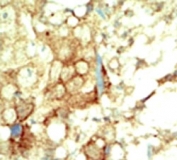

IHC analysis of FFPE human breast carcinoma tissue stained with the RET antibody

IHC (Paraffin) : 1:50-1:100